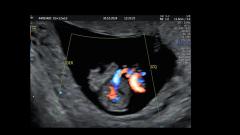

@diagnóstico 96